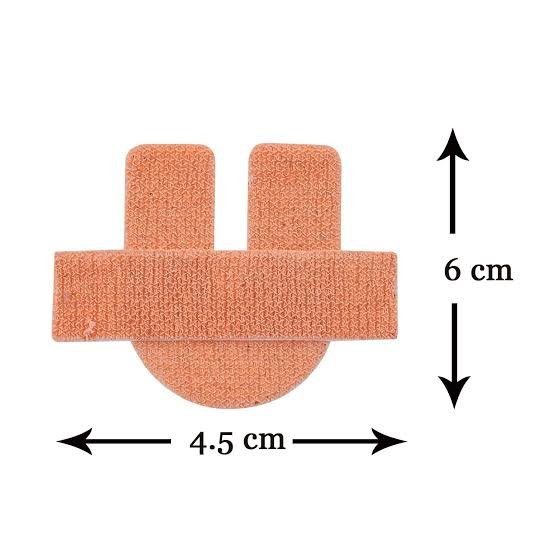

Cannula Fixator

Cannula FixatorOur ProductsFrom SurgicaveUplode:9 months ago from India